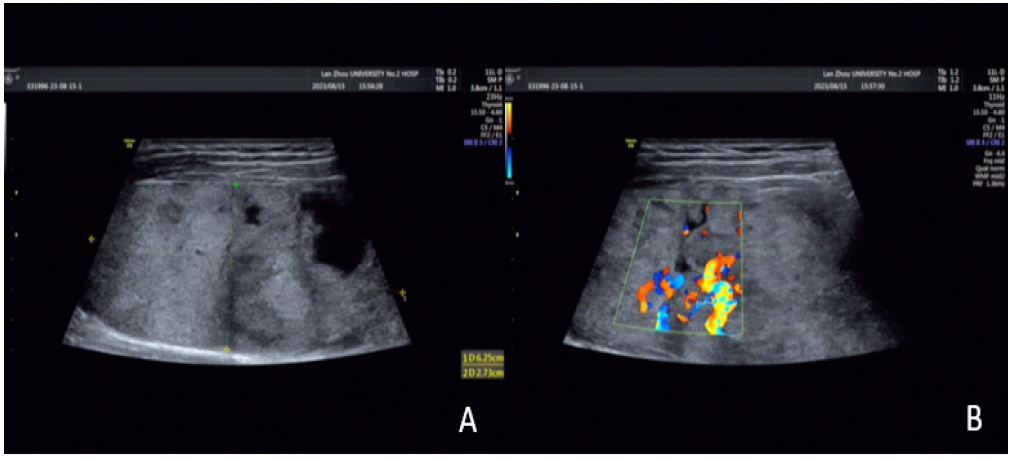

Imaging findings: 2D ultrasound revealed a 6.3 × 5.0 × 2.7 cm mixed-echo mass in the left thyroid lobe, with regular morphology, well-defined margins, heterogeneous echotexture, multiple anechoic areas, and abundant intratumoral vascularity (C-TIRADS 3). Contrast-enhanced neck CT suggested nodular goiter with possible follicular adenoma.

Figure 1: (A) A cystic solid mass of about 6.5 × 5.0 cm in size is seen in the left lobe of the thyroid gland (shown by arrows), with a regular morphology, clear borders, and heterogeneous internal echogenicity, and multiple irregular areas are seen; (B) abundant blood flow signals are seen inside and around the mass (shown by arrows).